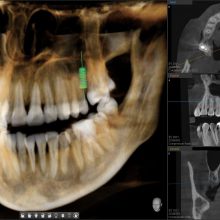

Компьютерная томография

Vatech